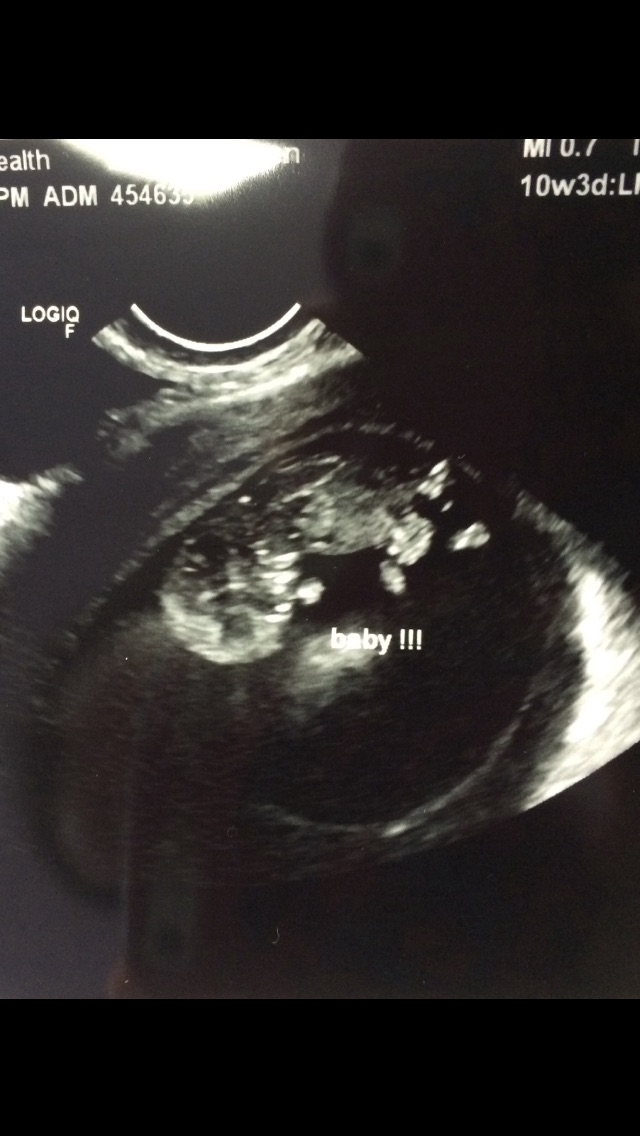

10 weeks US 176BPM it's amazing to see how much s/he moved!

I have a gender determination 3D ultrasound scheduled for Dec 17th (14w5d). Any thoughts if that's too early? The office told me they can do it as early as 12 weeks!?

• 10 weeks US 176BPM it's amazing to see how much s/he moved!